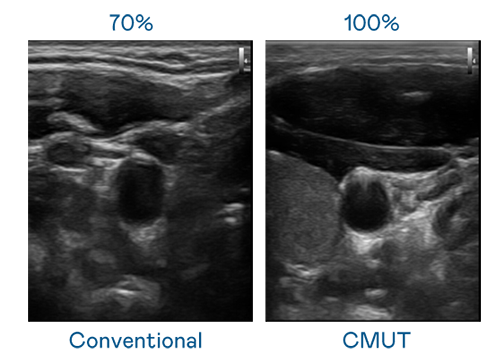

CMUT 技术是一种用电容式微机电元件来产生超音波讯号的技术。与传统 PZT 压电式技术相比,CMUT 频宽增加 30%,更宽频的超音波讯号让影像解析度大幅提升,是实现高影像品质医疗超音波扫描、促进精准医疗发展的关键技术。

大频宽带来超清晰影像

超音波影像的解析度高低,首先取决于探头能发出的讯号频宽。必一Bsports CMUT 可提供高清晰的超音波讯号,提供高频宽、高灵敏度、影像纹理细节更高的超音波影像,协助医护人员缩短影像判读时间及利用精准的医疗影像进行诊断。